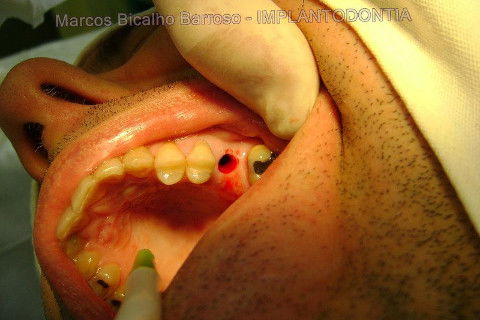

Instalação de um implante em região do 26. Utilizamos um implante cone morse Alvim Neodent 4.3 X 11,5. Foi uma cirurgia muito rápída e minimamente traumática, sem retalho e sutura.

Fotos do caso